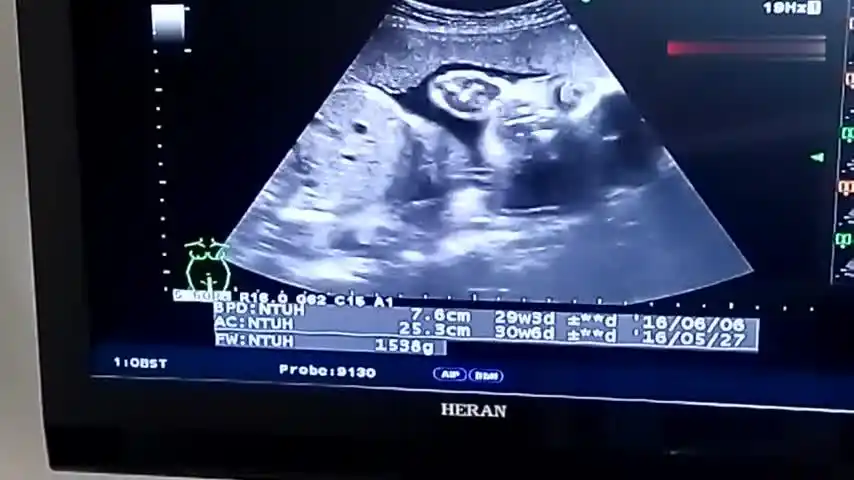

孕30周b超产检宝宝头偏小,医生安慰:女生头小说明脸小更漂亮!